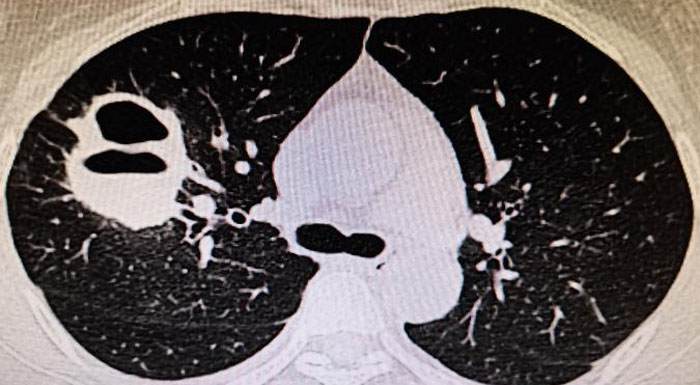

9、当肺CT出现如下情况,这可能是ANCA相关性血管肺部表现。